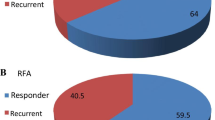

Lesion-based treatment response at mid-term (n = 46) according to mRECIST was CR in 21/46 (46 %), PR in 7/46 (15 %), SD in 14/46 (30 %), and PD in 4/46 (9 %). This resulted in a significant reduction of maximum lesion diameter from 24.9 mm (±13.3 mm) to 13.9 mm (±17.9 mm) (p > 0.0001).

Logistic regression was performed for ratios of all relevant arterial perfusion parameters (BV, BF, ALP, PBV) and baseline diameter according mRECIST for all treated HCC lesions with follow-up in CSI (n = 46). Regarding the regression model (1 = OR; 0 = SD or PD), best differentiation between groups was reached for ratios of BF (MS) and PBV with a sensitivity of 88 % and a specificity of 83 % in ROC analysis.